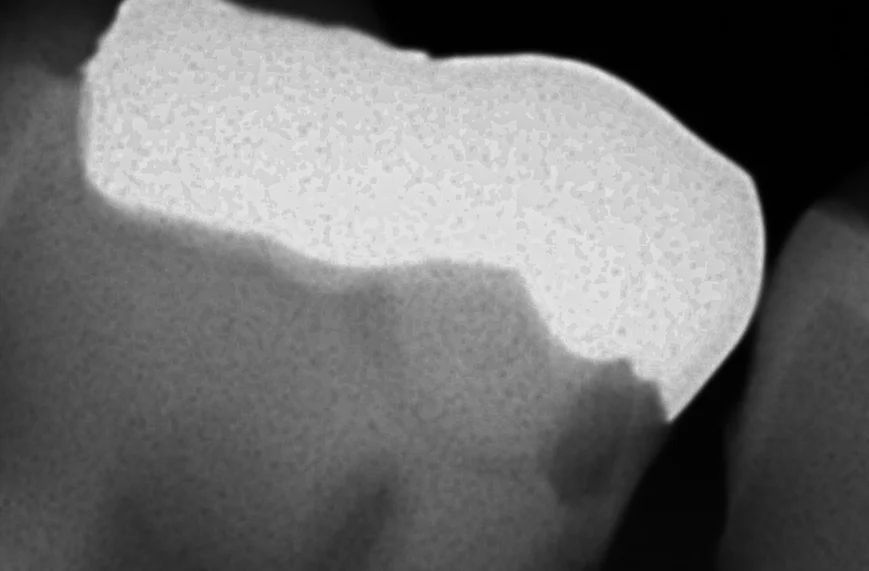

そして、術前術後のレントゲン写真がこちらです。

元がこちらですね。

金属の下が黒く抜けており、虫歯が内面で進行しているのが分かる状態になっています。

術前のレントゲン診査で、神経と虫歯が非常に近接している状態なのが分かっていましたから、ここは気を付けて処置を行いました。